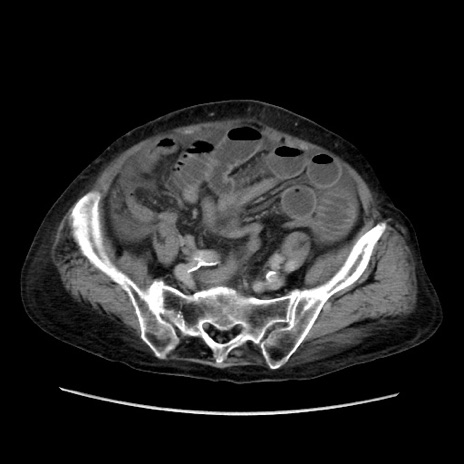

症例31(横断像)

【症例】80歳代 女性

【主訴】腹部膨満感

【現病歴】他院にて肝硬変にてフォロー中。1週間前から便秘、腹部膨満感、臍部腫瘤あり受診となる。

【既往歴】肝硬変

【身体所見】腹部膨隆あり、皮膚変化なし、疼痛なし。

【データ】WBC 4600、CRP 0.25